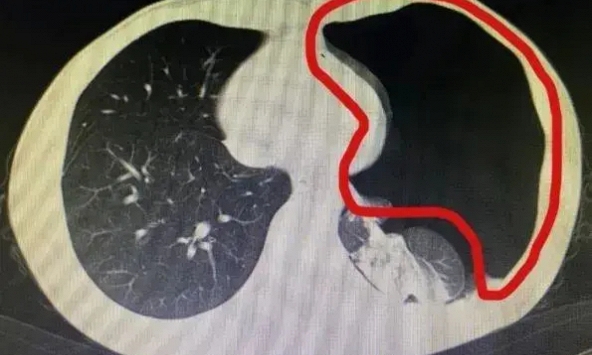

Người đàn ông sốt cao liên tục và hơn nửa lá phổi bị “ăn mất” chỉ vì 1 việc hầu hết chúng ta làm mỗi ngày

Ông Cương (Trung Quốc) không ngờ nguyên nhân khiến mình nhiễm trùng...